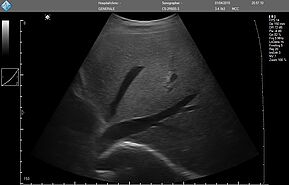

E-FAST имеет высокую чувствительность и специфичность (особенно в условиях гипотонии), может быть выполнен быстро, неинвазивно, без лучевой нагрузки, и может проводиться повторно. Благодаря таким преимуществам ультразвук по существу заменил диагностический перитонеальный лаваж (ДПЛ) при обследовании пациентов с травмой.

Положительный E-FAST у гемодинамически нестабильного пациента может указывать на необходимость проведения немедленного вмешательства (например, зондовой торакостомии, перикардиального окна, диагностической лапаротомии).

У гемодинамически стабильного пациента расширенная фокусированная оценка с сонографией при травме (E-FAST) может направлять дальнейшие диагностические исследования.

Хотя неотложный ультразвуковой протокол E-FAST был разработан для ускорения оказания помощи пострадавшим пациентам, применение его компонентов оказалось эффективным в случае использования портативного аппарата УЗИ (point-of-care ultrasound - POCUS) для обследования неповрежденных пациентов с гипотензией с целью выявления свободной жидкости, образовавшейся по другим причинам (например, при разрыве при внематочной беременности, аневризме брюшной аорты).